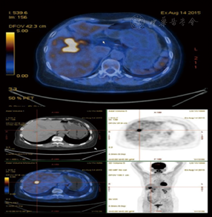

(1)病例特点:患者男性,69岁,因"胸闷不适5 d"于2015年8月6日就诊我院胸外科,正电子发射计算机断层显像(PETCT)提示:"肝右叶稍低密度肿块,考虑恶性可能大"(图1),以"肝占位"转入我科。既往史:否认肝炎病史。查体:无明显阳性体征。实验室检查:肿瘤标志物甲胎蛋白(AFP)、癌胚抗原(CEA)、CA19-9及其他生化检查未见明显异常。Child-Pugh分级为A级。B超及腹部增强CT均考虑恶性(图2,图3)。(2)治疗:手术行肝部分切除术,术中冰冻回报:考虑肝炎性肌纤维母细胞瘤。术后大体标本:呈黄白色、鱼肉状、质地较硬,似有包膜。(3)术后病理诊断为肝炎性肌纤维母细胞瘤。(4)预后:术后7个月门诊复查未见明显复发(图4),术后电话随访18个月未见明显复发表现,恢复良好。